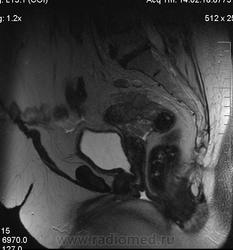

очень характерная картина для метастаза рака яичника, к сожалению.

Не могу достоверно определить локализацию метастаза брюшной полости, вероятно в лимф. узел с инвазией оободочной кишки. Рецидив С-r левого яичника думаю, что с инфильтацией левой стенки прямой кишки и культи влагалища, вторичная лимфаденопатия л/у малого таза. каликопиелоуретероэктазия (инвазия нижних отделов левого мочеточника?) Холедох широковат, но желтухи по внешнему виду нет.

Прорастание левого мочеточника рецидивной опухолью есть 100%, метастаз в большой сальник характерен для рака яичников, как и сигнальные характеристики его. Культя в данном случае шейки матки.